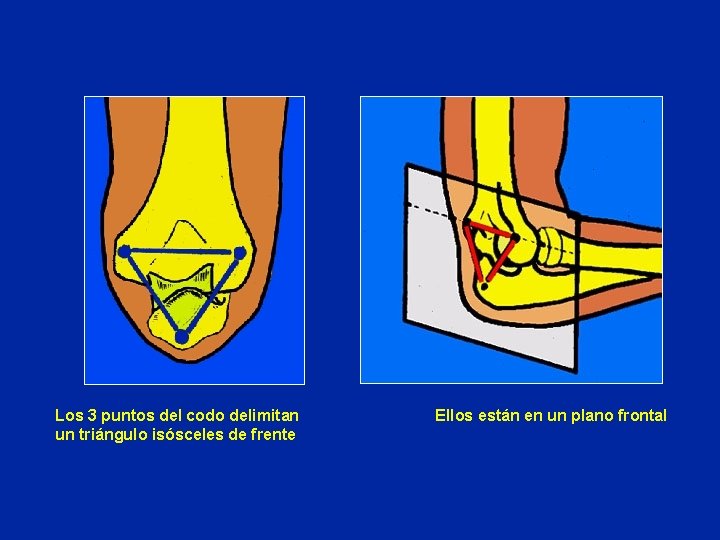

Examen: 3 puntos a localizar en el codo Epicóndilo, Epitróclea y Olécranon Alineamiento en extensión. Triángulo isósceles en flexión.

Los 3 puntos del codo delimitan un triángulo isósceles de frente Ellos están en un plano frontal

PALPACION Anterior: • Relieve de la tróclea Posterior: • Olécranon • Cúpula radial • Los 3 puntos del codo se modifican